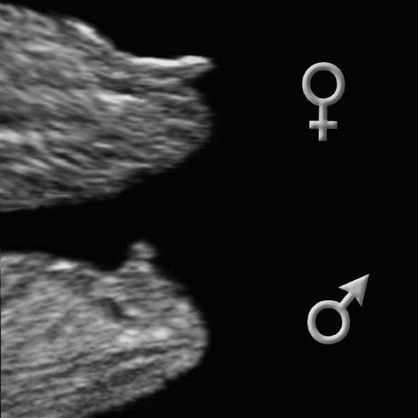

на этом сроке и у мальчиков и у девочек такой вот отросточек. Надо сбоку смотреть по его наклон. ВОт есть такая картинка, как отличить

Недавно только читала как врачи определяют пол на таких сроках, мол, если торчит на 90° - то скорее всего мальчик, а если на 45° вниз то скорее всего девочка))